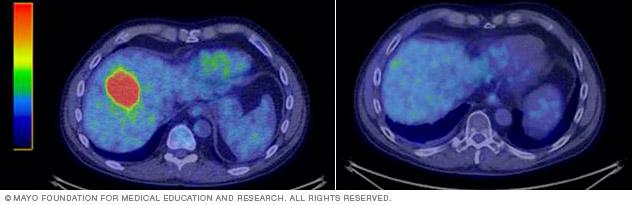

Tumor in the liver before (left) and after (right) stereotactic body radiotherapy.

The effects of SBRT happen over a period of time. What happens after treatment depends on the condition being treated and the location of the target. SBRT might result in the following:

• For noncancerous targets, the goal is often to stop growth or reduce activity of the target. The target may shrink slowly with time. Or it may stay the same size and that may still be considered a good response.

• For cancerous targets, the treated tumor may shrink with time, or it may stop growing. Changes are not always seen right away. Early imaging can sometimes show temporary swelling or inflammation related to treatment.